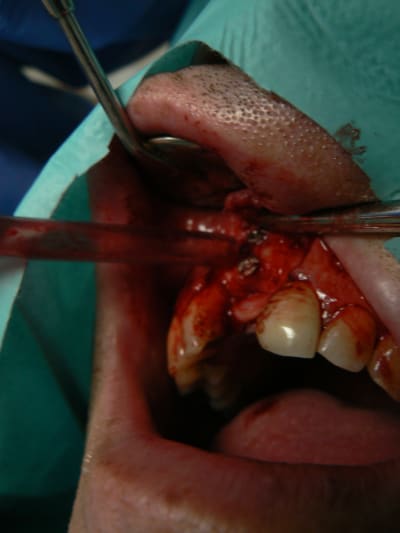

J'ai simplement peur que les vis de transfixation du greffon ne puissent provoquer son décollent au moment de leur dépose. En effet si de l'os vient se recréer entre les trois tétons, lors du dévissage ça peut provoquer un mouvement du greffon.

Bravo

sur les photos je vois que j'utilise la meme pince à broyer l'os que toi, mais lors de ma première utilisation, j'ai constaté que les sommets des petites pointes acier se sont cassées et des tous petits morceaux se sont retrouvé dans mon broyat osseux... bref pas glop, surtout que le godet inférieur s'est déssoudé, bref j'ai eu une première impression très négative! du coup je suis retourné au broyeur à impaction, mais j'aimerais avoir ton impression...